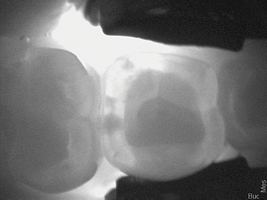

A 38-year-old female patient with incipient decay discovered on a transillumination caries detection device image (Figure 5 and Figure 6) presented for her bi-annual hygiene visit. The doctor was considering whether to treat the decay with a restoration or to "watch it." He decided that instead of monitoring the lesion, he could treat it with silver diamine fluoride, possibly halting the decay and hardening the lesion. The patient was informed of the possibility the decay would turn black; however, the decay process could halt, and she would not need a filling in the future. She was pleased at the prospect her tooth would remain intact without needing restorative treatment. After signing the consent form, she opted for treatment that day in the hygiene visit. She was appointed for one week later for the re-application of the silver diamine fluoride and advised that it may need to be reapplied one to two times per year.

(5.)  Incipient decay on tooth No. 29.

Figure 5

(6)  Incipient decay on tooth No. 20.

Figure 6